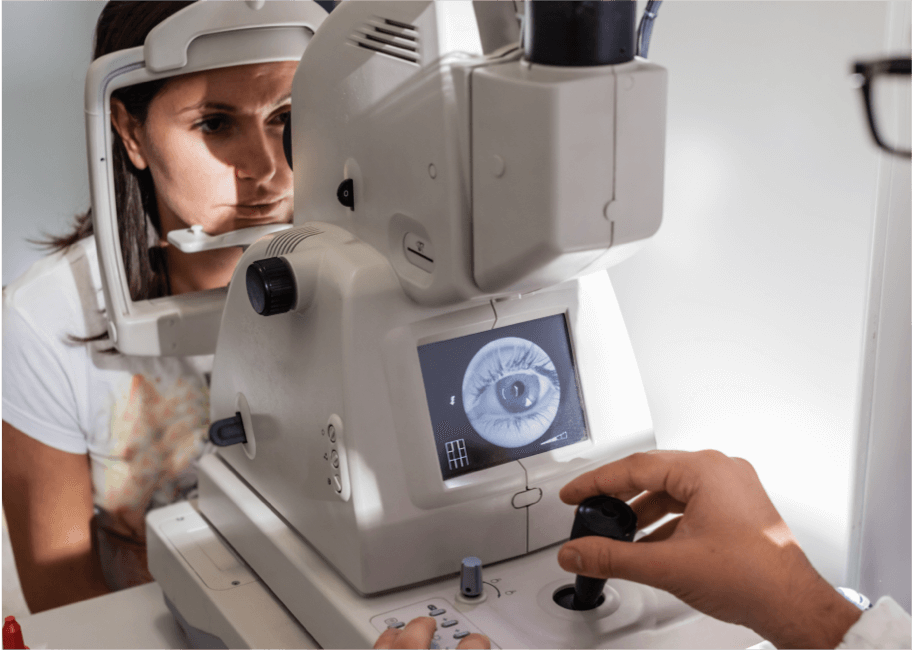

Untersuchung des Augenhintergrunds

Bei der Untersuchung des Augenhintergrunds handelt es sich um einen umfassenderen Test zur Diagnose der AMD. Dies ist eine optische Untersuchung der Netzhaut im hinteren Teil des Auges. Das Wort „Augenhintergrund“ bzw. „Fundus“ ist der medizinische Fachausdruck für den Teil des Auges, der sich am weitesten von der Öffnung entfernt befindet, also in diesem Fall die Rückseite des Auges. Die Untersuchung des Augenhintergrunds kann entweder mittels einer Ophthalmoskopie oder einer Fundusfotografie durchgeführt werden.2 Bei beiden Methoden werden dem Patienten pupillenerweiternde Tropfen verabreicht, damit die medizinische Fachkraft den hinteren Teil des Auges besser sehen kann.4

Ophthalmoskopie

Bei dieser Methode der Augenuntersuchung leuchtet die medizinische Fachkraft mit einem hellen Licht durch die geweitete Pupille, und ein Ophthalmoskop erstellt vergrößerte Bilder der Netzhaut. Die Ophthalmoskopie ist ein wichtiges Instrument zur Diagnose der AMD, da sie es der medizinischen Fachkraft ermöglicht, Anomalien der Netzhaut wie Atrophie, Drusen, Pigmentveränderungen und choroidale Neovaskularisationen (CNV) zu erkennen.5,6 Es gibt drei Arten der Ophthalmoskopie.

Ophthalmoskopie mittels Spaltlampe

Diese Art der Untersuchung wird üblicherweise zur Diagnose von AMD verwendet und mit einem ophthalmologischen Mikroskop mit Spaltlampe durchgeführt.5 Das Kinn des Patienten ruht auf einem Spaltlampengerät, Licht wird durch einen schmalen Spalt in das Auge des Patienten geschickt und der Arzt untersucht den Augenhintergrund mithilfe einer Lupe.5